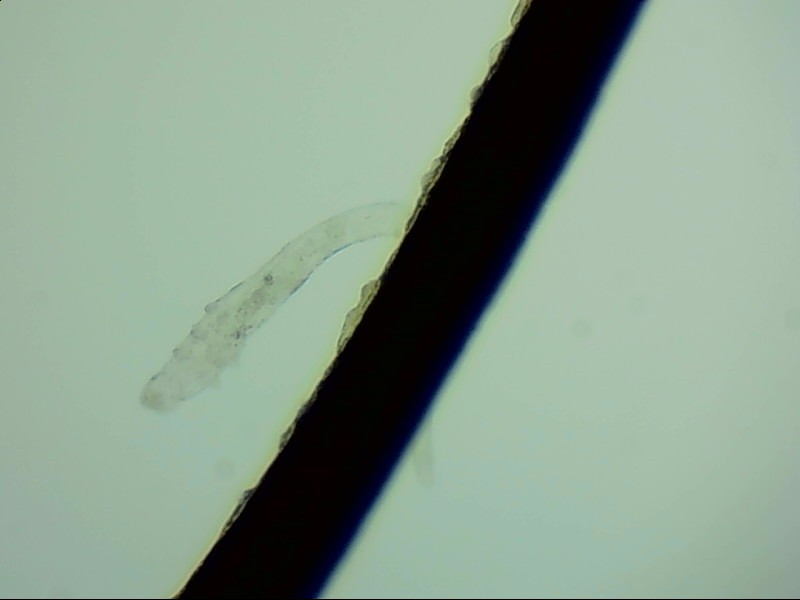

小張是一位程序員,長(zhǎng)時(shí)間對(duì)著電腦,感覺(jué)眼干、有異物感在所難免。最近他除了眼干、難受,還發(fā)現(xiàn)眼睛發(fā)癢,掉落的睫毛上還會(huì)帶著絲狀的分泌物。剛發(fā)現(xiàn)時(shí)小張并沒(méi)有放在心上,但當(dāng)他在屏幕上看到睫毛上的螨蟲時(shí),他的心里一陣后怕,“原來(lái)我的睫毛上長(zhǎng)著這么可怕的東西。”

螨蟲怎么會(huì)爬到睫毛里?廈門眼科中心蠕形螨性瞼緣炎門診張麗穎博士后介紹,人體螨蟲主要有兩種,一種是皮脂螨,主要寄生于皮脂腺和瞼板腺內(nèi);另一種是蠕形螨,“住”在睫毛毛囊里,晚上從毛囊里爬出來(lái),白天躲在毛囊里產(chǎn)卵。

據(jù)介紹,這種疾病確診主要通過(guò)觀察睫毛里的螨蟲數(shù)量聯(lián)合瞼緣及眼表情況共同診斷。一般而言,如果12根睫毛里,有2條或是超過(guò)2條的螨蟲就可以被確診。如果檢查確實(shí)發(fā)現(xiàn)較多的蠕形螨感染,建議加上抗螨治療。張麗穎說(shuō),發(fā)現(xiàn)眼睛干澀、發(fā)癢,不要自行用藥,建議到醫(yī)院就診。如果長(zhǎng)期反復(fù)多發(fā)霰粒腫,要考慮是否存在蠕形螨感染。